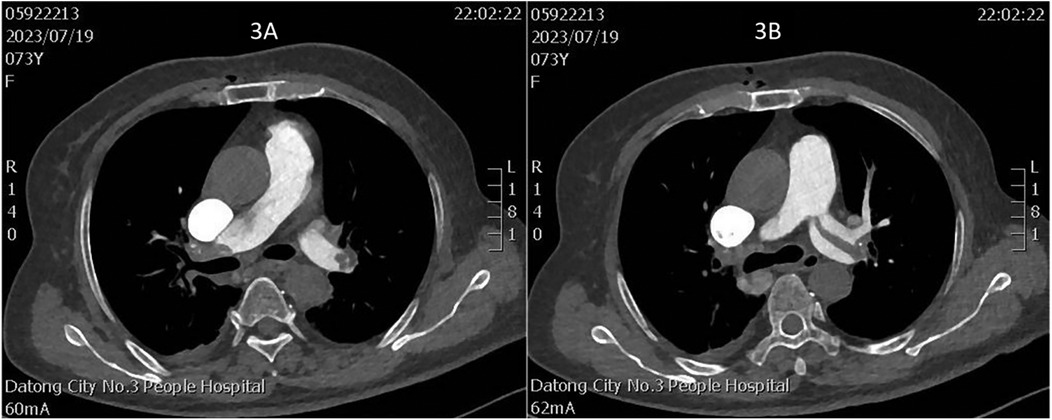

On July 17, a dual-chamber pacemaker (St. Jude Medical PM2172) was implanted via the right subclavian vein under standard parameters: atrial impedance 652 Ω, threshold 1.0 V, P-wave amplitude 10.6 mV; ventricular impedance 768 Ω, threshold 0.5 V, R-wave amplitude 13.6 mV. Strict immobilization of the operative-side upper limb was required within 24 h after surgery. During this period, patients were absolutely prohibited from raising the affected arm above shoulder level and from using the operated-side arm to support themselves when getting out of bed. Additionally, patients were instructed to avoid lying on the surgical side and were encouraged to begin ambulation starting 3 h after surgery. With the day of surgery designated as postoperative day 1 (POD1). By POD2, the incision site remained dry and showed no signs of pocket swelling. At 47 h post-implantation, the patient experienced syncope during ambulation, accompanied by hypotension (76/50 mmHg), tachycardia (110 bpm), tachypnea (30–40/min), and hypoxemia (SpO2 82%). D-dimer surged to 1,617 μg/L. Electrocardiographic findings included VAT (Ventricular pacing, Atrial sensing, and Triggered response) pacing mode with accelerated idioventricular rhythm and atrioventricular dissociation (Figure 2). Device interrogation revealed atrial sensing failure and elevated thresholds, prompting transition to VVI pacing (Table 1). Bedside echocardiography at 18:50 showed: right ventricular enlargement (30 mm), paradoxical motion of the interventricular septum, and moderate pulmonary hypertension (tricuspid peak systolic pressure gradient >60 mmHg). Based on the patient's symptoms, signs, and relevant examinations, the possibility of acute pulmonary embolism was considered high, and immediate treatments were administered, including oxygen inhalation, approximately 800 ml of fluid replacement, and norepinephrine for blood pressure elevation. After the vital signs became slightly stable (blood pressure: 98/60 mmHg, heart rate: 100 beats per minute, respiratory rate: 25 breaths per minute, blood oxygen saturation: 92%), a pulmonary computed tomography angiography (CTA) performed at 22:10 confirmed bilateral pulmonary artery emboli (Figure 3). The patient was transferred to the ICU at 22:30. Alteplase (50 mg) thrombolysis initiated at 23:17 (POD3) yielded rapid symptomatic improvement (SpO2 98% on 5 L/min O2 within two hours). Subsequent low-molecular-weight heparin (5,000 U subcutaneously every 12 h) was administered. By POD3, fresh hemorrhage and pocket distension necessitated intermittent compressive dressing (10 h compression/2 h release for four days, transitioning to 6 h cycles thereafter). On the second day after thrombolysis (POD4), tumor markers were measured in the patient, and the results showed that alpha-fetoprotein (AFP), carcinoembryonic antigen (CEA), carbohydrate antigen 125 (CA125), carbohydrate antigen 15-3 (CA15-3), and squamous cell carcinoma antigen (SCCA) were all within the normal range. The pocket ecchymosis measured approximately 20 cm × 15 cm, but no skin necrosis occurred. No hemorrhage was observed in other organs. Changes in hemoglobin levels are shown in Figure 4. Despite periprocedural ecchymosis, lower extremity ultrasonography on POD8 revealed bilateral calf muscular venous thrombosis. Warfarin anticoagulation commenced on POD9, maintaining an INR of 2–3. The incision healed without complication by POD12. A follow-up echocardiogram on POD8 revealed only a small amount of tricuspid regurgitation. Follow-up evaluations at 28 days and three months post-discharge demonstrated stable pacemaker function (Table 1), resolved pulmonary emboli, and reduced right atrial dimensions (73.4 × 51.5 mm to 43.0 × 42.2 mm; Figure 5). The key time points of the patient are shown in Figure 6.

Figure 3

Two CT scan images labeled 3A and 3B show cross-sectional views of the chest, highlighting internal anatomical structures. Both scans display details of bones, soft tissues, and visible contrasts in the chest cavity, conducted at Datong City No. 3 People Hospital.

Figure 3. (A) Thrombus in the right main pulmonary artery; (B) thrombus in the left main pulmonary artery.